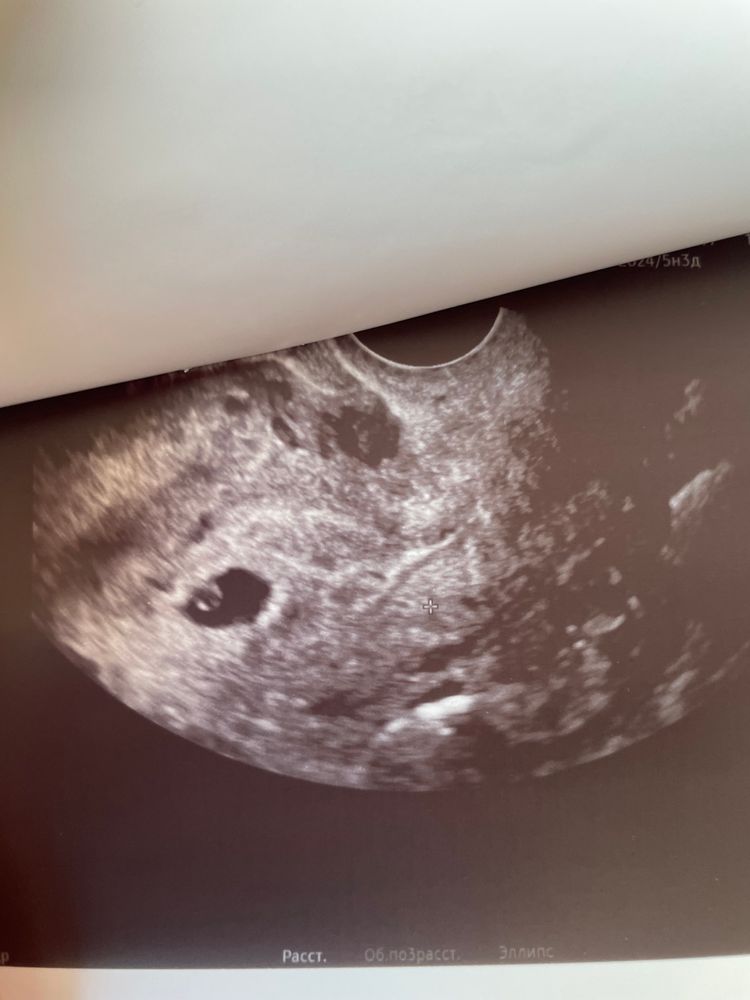

24 ДПО. Он же 3 день 5 недели. УЗИ и ТТГ

1. Режим паникер активен. Чувствую дискомфорт в животе - паника, ничего не чувствую - паника. В итоге не удержалась и пошла вновь на УЗИ. Вс] отлично, увидели и ЖМ, и даже очень маленький эмбриончик. Ура! Надо обуздать свои переживалки и спокойно посидеть две недели.